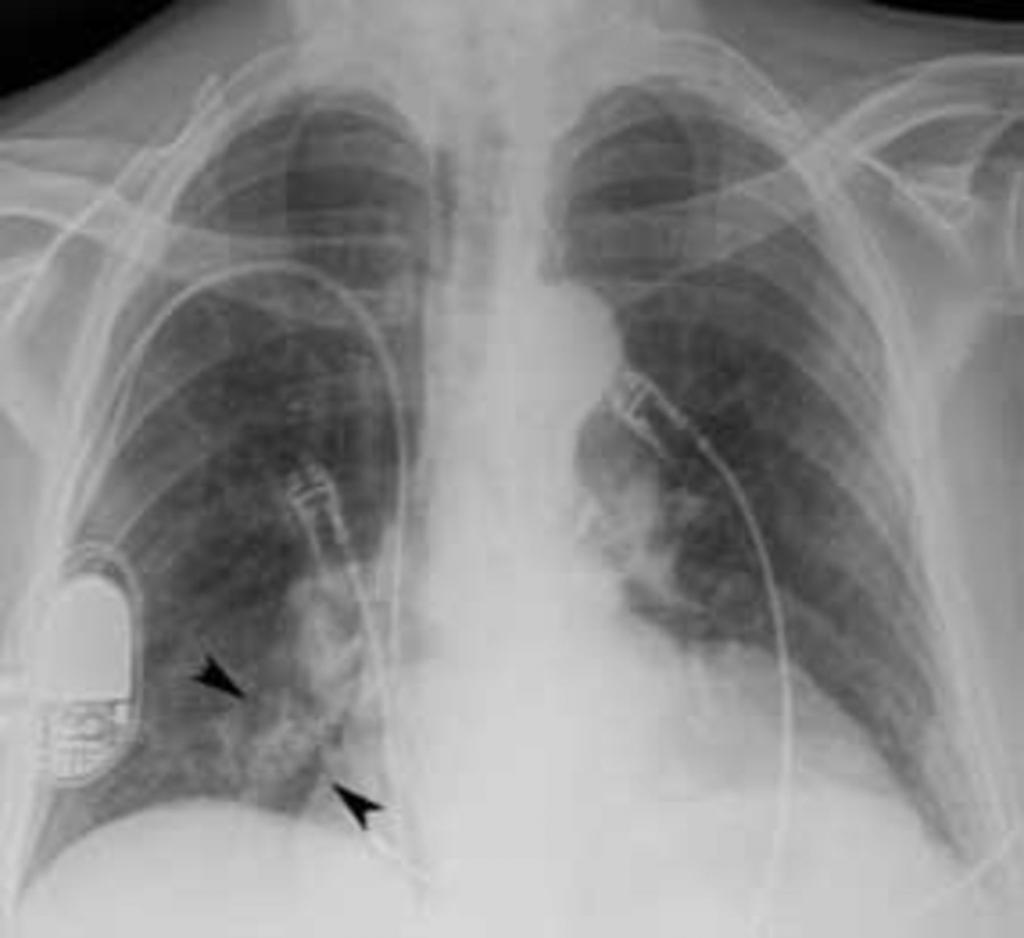

При плеврите, на снимке скопление экссудата в поражённой области. Плеврит выступает в качестве осложнения недолеченной пневмонии.

- при воспалении плевры прослеживается линейная тяжистость, жидкость в реберно-диафрагмальном синусе на боку патологии;

- закупорка реберно-диафрагмальных синусов жидкостью;

- завуалированность реберно-диафрагмального синуса.